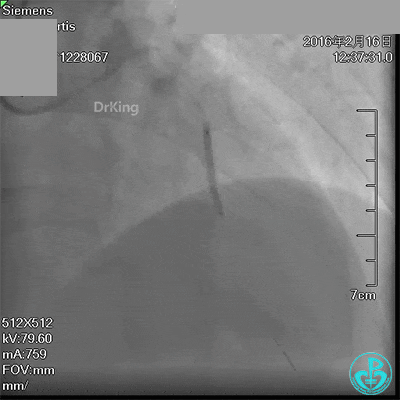

急诊术中导丝在锁骨下通过困难,曾在局部推注造影剂造影,回顾造影结果发现局部小血管破裂造影剂渗漏。